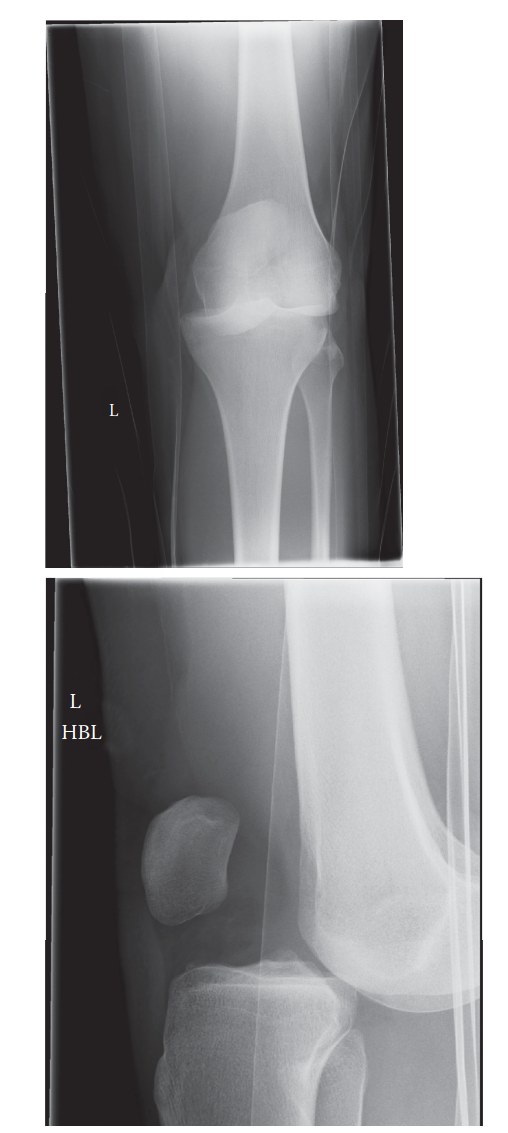

Initial radiographic evaluation focuses on determining the direction of the dislocation and identifying concomitant bony injuries, such as avulsion fractures (e.g., Segond fracture, fibular head avulsion) or periarticular fractures.

Anteroposterior (AP), lateral, and oblique views must be obtained immediately before and after reduction.

Figure 1: Anteroposterior (AP) radiograph demonstrating a gross lateral knee dislocation with complete loss of tibiofemoral articulation.

Figure 2: Lateral radiograph of the same patient confirming the severe displacement and disruption of the joint axis.

Following successful closed reduction and stabilization (often via a knee immobilizer or external fixator), advanced imaging is required.